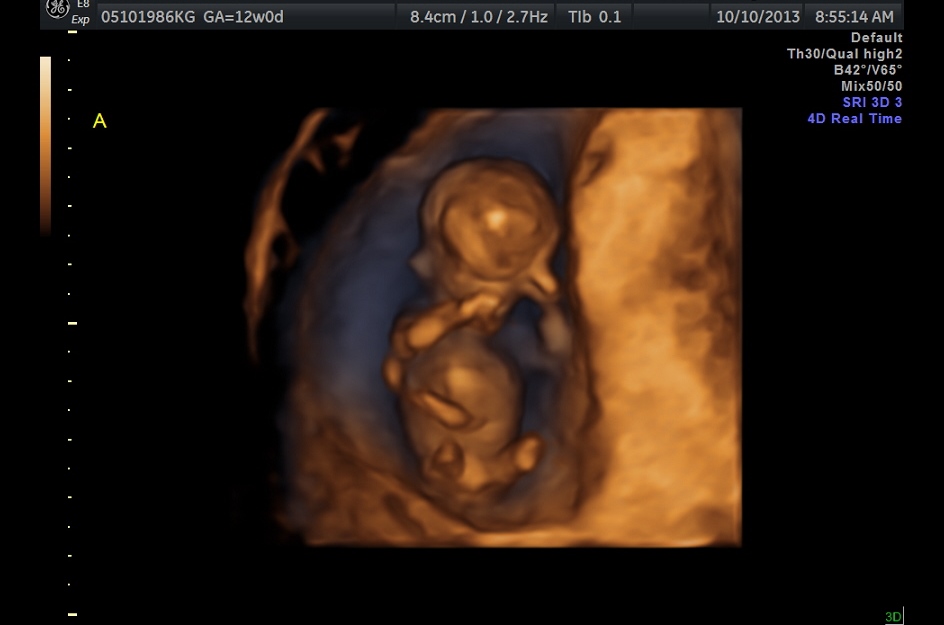

4D pictures from Today's NT Scan

We have two fraternal (yay low high risk pregnancy!) very healthy babies.  Their brains look great, their hearts look great, and they don't seem to be at any risk for Down Syndrome (Going in for blood work tomorrow).  We got to see their long legs and take a good look at arms, hands, and face.  Also we heard their hearts beating for the first time.  Magical.

-Second one is baby B, caught in the act of staying still for once

-Third one is the two of them together, baby A is to the right and B is on the lower left.